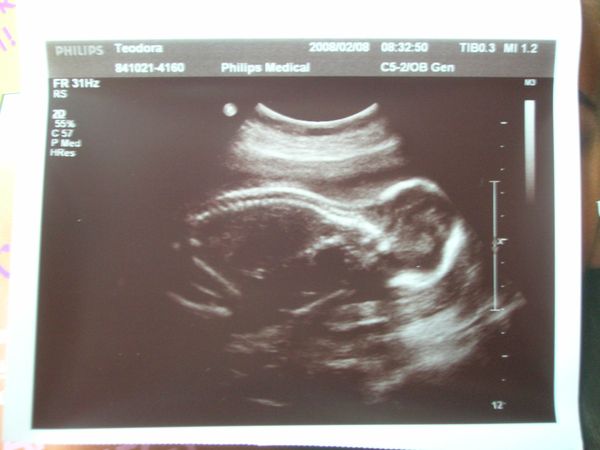

babó hason